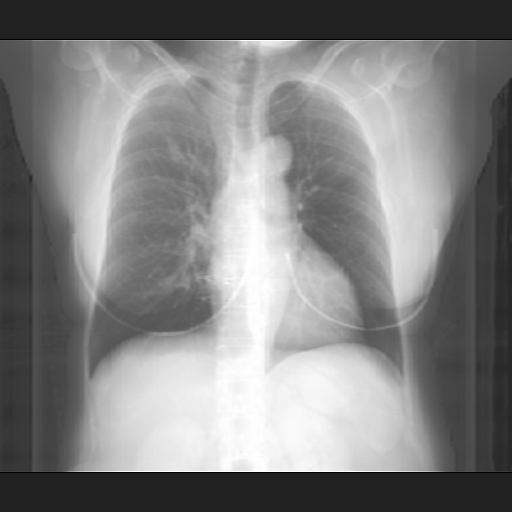

We compare our projected X-Rays with samples from the OpenI dataset for frontal and lateral views in Figure 5. The differences in the frontal view are due to the different positioning of the shoulder girdle. In the X-Rays, the arms are usually placed alongside the body, while in the projected images, the arms are raised due to the nature of the CT scan. In the lateral view, the X-Rays show a more comprehensive range of orientation and pose. However, the projected images, typically taken while the patient is lying down, result in similar poses between the different images. This leads to visual differences between images of female patients in both frontal and lateral views, such as the third column and second row of real X-Ray images and the first column and second row of projected images.